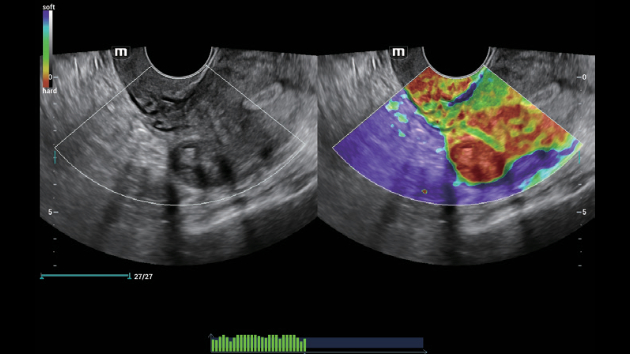

Powered by ZST +

The ZST+ platform represents an extraordinary leap forward in ultrasound technology, moving away from traditional beam-forming to channel data processing. This groundbreaking innovation overcomes the traditional trade-offs among spatial resolution, temporal resolution, and tissue uniformity, resulting in unparalleled image quality that empowers infinite imaging solutions.